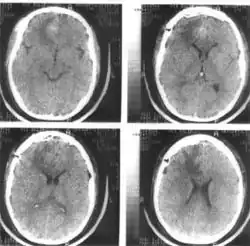

Компьютерная томография (КТ) и магнитно-резонансная томография (МРТ) — наиболее важные диагностические исследования при инсульте. КТ в большинстве случаев позволяет чётко отдифференцировать «свежее» кровоизлияние в мозг от других типов инсультов, МРТ предпочтительнее для выявления участков ишемии, оценки распространённости ишемического повреждения и пенумбры. Также с помощью этих исследований можно выявлять первичные и метастатические опухоли, абсцессы мозга и субдуральные гематомы. Если наблюдается ригидность затылочных мышц, но отсутствует отёк диска зрительного нерва, люмбальная пункция в большинстве случаев позволит быстро установить диагноз кровоизлияния в мозг, хотя при этом сохраняется незначительный риск возникновения синдрома «вклинения» мозга. В случаях, когда есть подозрения на эмболию, люмбальная пункция необходима, если предполагается применение антикоагулянтов. Люмбальная пункция имеет также важное значение для диагностики рассеянного склероза и, кроме того, может иметь диагностическое значение при нейроваскулярном сифилисе и абсцессе мозга[39]. При недоступности КТ или МРТ необходимо выполнить эхоэнцефалографию и люмбальную пункцию.